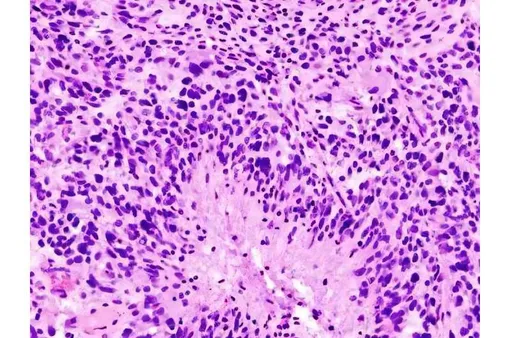

Особенность глиобластомы в том, что она не просто растет сама по себе, а перепрограммирует здоровые клетки мозга. Опухоль создает вокруг себя сложную сеть, которая питает ее, защищает и помогает распространяться.

Оказалось, что все дело в олигодендроцитах. Обычно они изолируют нервные волокна, то есть обматывают отростки нейронов специальным веществом — миелином, — чтобы электрические сигналы в мозге передавались быстро и четко. Но в присутствии глиобластомы они начинают активно общаться с раковыми клетками, посылая им химические сигналы, которые укрепляют опухоль, помогают ей расти и выживать.